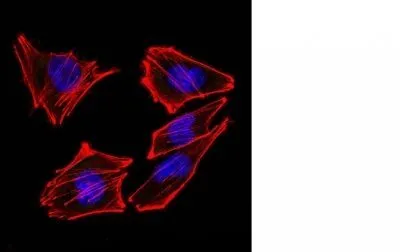

- Description: S100 belongs to the family of calcium binding proteins. S100A and S100B proteins are two members of the S100 family. S100A is composed of an alpha and a beta chain whereas S100B is composed of two beta chains. This antibody is specific against an epitope located on the beta-chain (i.e. in S-100A and S-100B) but not on the alpha-chain of S-100 (i.e. in S-100A and S100A0). This antibody can be used to localize S-100A and S-100B in various tissue sections. S-100 protein has been found in normal melanocytes, Langerhans cells, histiocytes, chondrocytes, lipocytes, skeletal and cardiac muscle, Schwann cells, epithelial and myoepithelial cells of the breast, salivary and sweat glands, as well as in glial cells. Neoplasms derived from these cells also express S-100 protein, albeit non-uniformly. A large number of well-differentiated tumors of the salivary gland, adipose and cartilaginous tissue, and Schwann cell-derived tumors express S-100 protein. Almost all malignant melanomas and cases of histiocytosis X are positive for S-100 protein._x000D__x000D_Primary antibodies are available purified, or with a selection of fluorescent CF® Dyes and other labels. CF® Dyes offer exceptional brightness and photostability. Note: Conjugates of blue fluorescent dyes like CF®405S and CF®405M are not recommended for detecting low abundance targets, because blue dyes have lower fluorescence and can give higher non-specific background than other dye colors.

- Cellular Locus: Cytoplasmic|Nucleus|Vesicular

- Applications: IF (verified) | IHC, FFPE (verified)

- Validated Applications: IF, IHC, FFPE

- Additionnal Information: Higher concentration may be required for direct detection using primary antibody conjugates than for indirect detection with secondary antibody|Immunofluorescence: 1-2 ug/mL|Immunohistology formalin-fixed 0.25-0.5 ug/mL|Staining of formalin-fixed tissues requires boiling tissue sections in 10 mM citrate buffer, pH 6.0, for 10-20 min followed by cooling at RT for 20 minutes|Flow Cytometry 0.5-1 ug/million cells/0.1 mL|Western blotting 0.5-1 ug/mL|Optimal dilution for a specific application should be determined by user